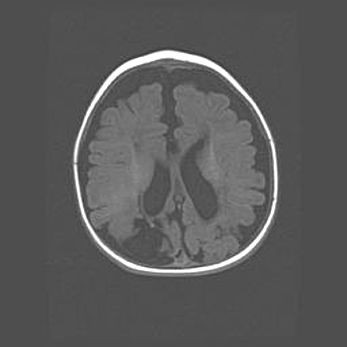

Церебральная ишемия II.

Возраст: 5 дней

Вес: 3400 г

Пол: женский

Окружность головы: 35 см

Срок гестации: 39 недель

Церебральная ишемия – это заболевание, характеризующееся недостаточностью (гипоксией) либо полным прекращением (аноксией) снабжения мозга кислородом по причине закупорки одного или нескольких сосудов. Это приводит к  что метаболическим расстройствам различной степени тяжести в тканях головного мозга, развитию коагуляционных некрозов и гибели нейронов.